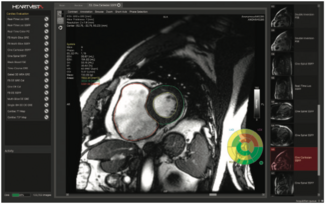

HeartVista’s October 2019 FDA clearance for its One Click Cardiac MRI package was announced against the backdrop of the June 2019 publication of the MR-INFORM trial in the New England Journal of Medicine.